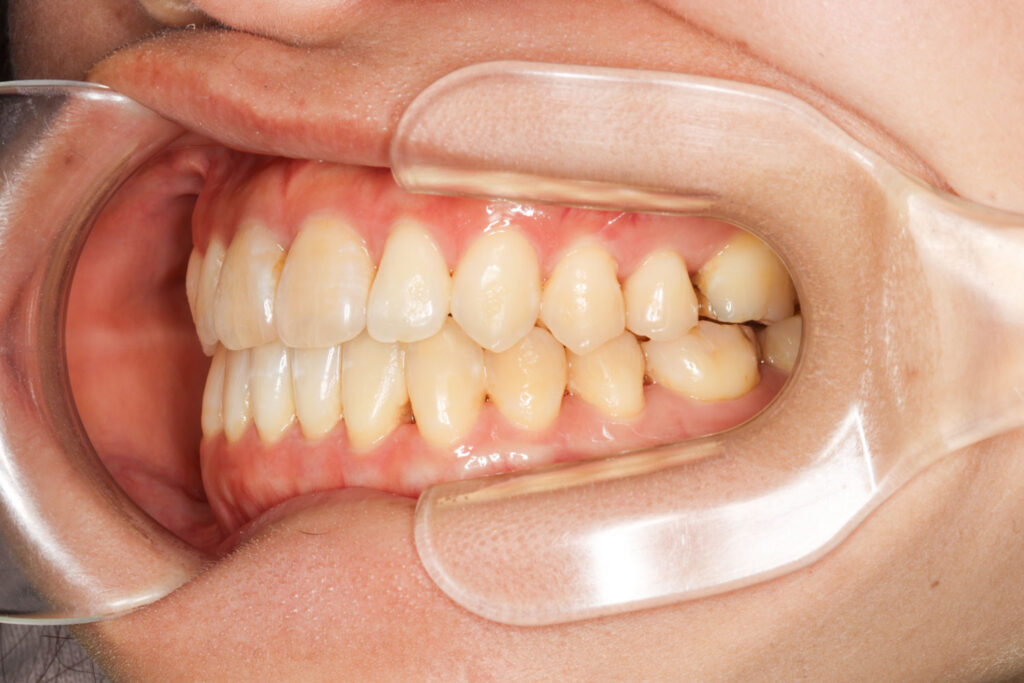

Before

After

年齢 10代

治療装置 上は裏側の矯正装置(フルリンガル)

治療内容 非抜歯

治療期間 2年8か月

リスク 歯の移動に伴う痛み、歯肉退縮、歯根吸収、歯肉炎、虫歯

主訴 ガタガタと隙間が気になる

症状 叢生と正中離開

治療回数 36回程度

総額費用 140万円程度